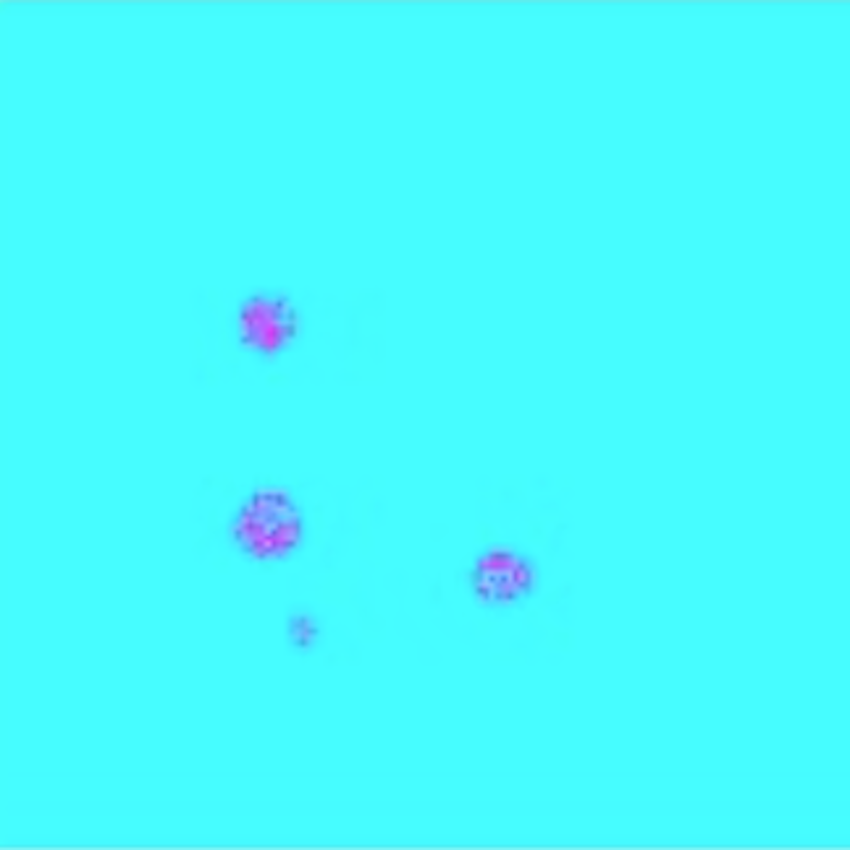

In this paper, we present U-LanD, a novel uncertainty-driven video landmark detection framework. U-LanD is specifically designed to consider the bias in sparsely annotated video data and automatically detect the location of landmarks on the key frames of the video. U-LanD is based on a core observation: a deep Bayesian encoder-decoder network only trained on labelled key frames, shows significantly higher prediction confidence (lower uncertainty) in test time when deployed on key frames vs. non-key frames, as illustrated in Fig 1. U-LanD exploits the test-time predictive uncertainty as an unsupervised guiding signature to detect landmark points on key frames. U-LanD considers several aspects of predictive uncertainty in landmark detection, namely i) contextual quality control based on landmark heatmaps; ii) pixel-level epistemic uncertainty with variational dropout; and iii) pixel-level heteroscedastic aleatoric uncertainty by placing a Gaussian distribution over the observed labels.

To generate the ground-truth masks for training, we place a circle with radius at the coordinates of landmarks, where is a hyperparameter tuned to account for the inter-observer variability in landmark labels. Here for the purpose of demonstration, we adapt a circle formation, while more complex choices of ground-truth genesis based on the underlying object could be investigated [30]. At test time, the center of gravity (COG) of the predicted heatmaps are used to obtain the coordinates of the landmarks. The BU-Net, only trained on key frames, generally produces valid predictions in vicinity of the key frames, and produces invalid predictions for non-key frames, where it shows an unseen event or the object of interest does not have clear visibility. Therefore, the prediction quality based on the interpretation of the heatmaps could be used as a criterion to detect the key frames discussed next.

The predicted heatmaps by the detector are passed through a sanity check to discard non-valid predictions, which correlate to non-key frames. Each key frame has landmark points, where each point is marked in the ground-truth mask with a circle of radius . We perform a spatial sanity check on the predicted heatmap of each frame by locating all blobs with radius ; if heatmaps are located in the prediction, and , the frame is discarded as a non-key frame. The BU-Net predictions tend to be invalid the further you move from the key frames, i.e., the detector fails to predict enough heatmaps () or predicts multitude of noisy heatmaps (). After this initial contextual sanity check based on the prediction heatmap, the remaining candidate key frames are assessed in terms of predictive uncertainty. The two major sources of predictive uncertainty considered are epistemic and aleatoric.

| a) Sample Non-key Frame | Epistemic | Aleatoric | |

| b) Sample Key Frame | Epistemic | Aleatoric | |